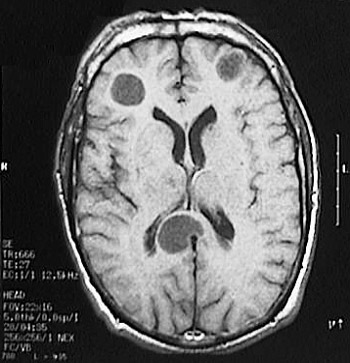

Click on one of the larger metastases in the MRI scan above:

This magnetic resonance imaging (MRI) scan of the head in transverse (axial) view reveals the presence of several centrally cystic, well-circumscribed metastatic tumor nodules in the brain.